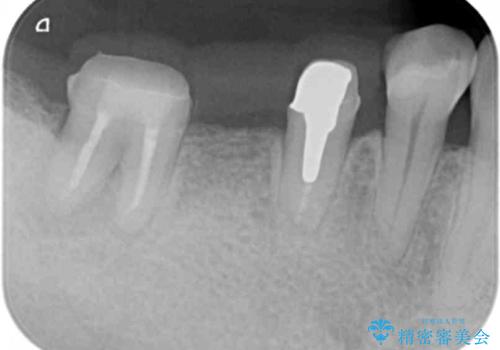

X線写真より歯の神経組織が壊死し、根尖周囲に病変を作り透過像を呈している状態でした。

咬合痛の原因となっている右下第2大臼歯の根幹治療を行ったのち、強度に優れるフルジルコニアクラウンによる咬合機能回復を計画します。